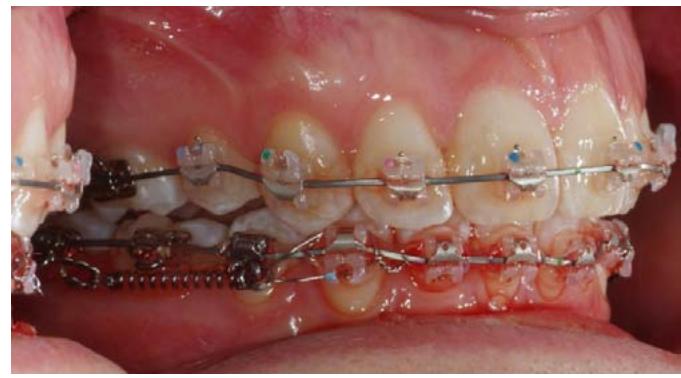

L'ancrage est mis en traction par un ressort NiTi de 300 grammes mis en place de façon simple après l'intervention. L'extrémité postérieure du ressort NiTi est fixée sur la partie toronnée du fil d'osteosynthèse.

L'extrémité antérieure du ressort est connectée à l'appareil multi bagues inférieur par une ligature métallique. Il s'agit dans ce cas d'une traction directe.

Dans le cas de notre paciente, la distalisation débute sur un arc à mémoire de forme de section.020 x.020.

Vue du système de traction du côté droit, gauche, puis en vue occlusale.